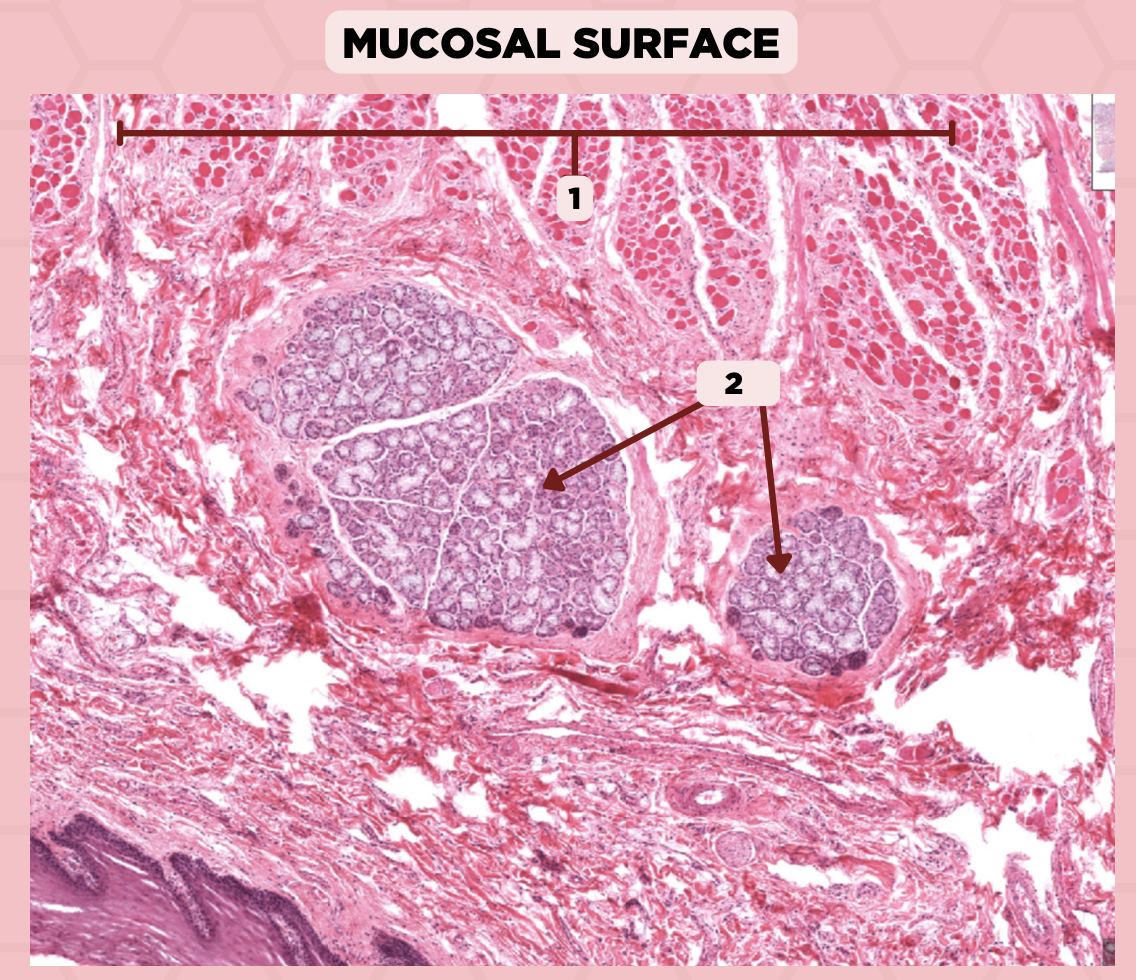

Lip

What specimen is showed in the picture?

Labial Glands (in the Mucosa)

Identify the structure labeled as 1.

Skeletal Muscle Cells

Identify the structure labeled as 2.

Lamina Propria

Identify the structure labeled as 3.

Mucosa

Identify the structure labeled as 4.

Lip

What specimen is showed in the picture?

Skeletal Muscle Fibers

Identify the structure labeled as 1.

Labial Glands

Identify the structure labeled as 2.